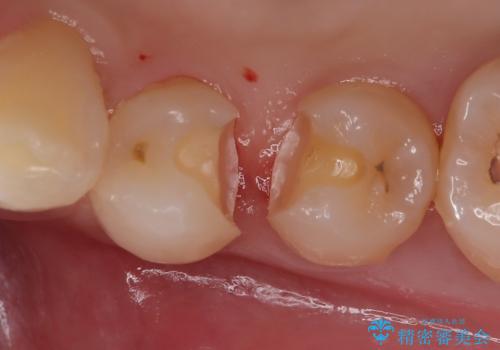

- 左下の第1・第2小臼歯の接触面にカリエスを認めました。

隣接面のため肉眼での確認が難しく、レントゲンにて診断を行ったのち、

マイクロスコープを使用して虫歯を丁寧に除去。

歯質の保存と適合精度、そして審美性を考慮し、セラミックインレーによる修復を行うこととしました。